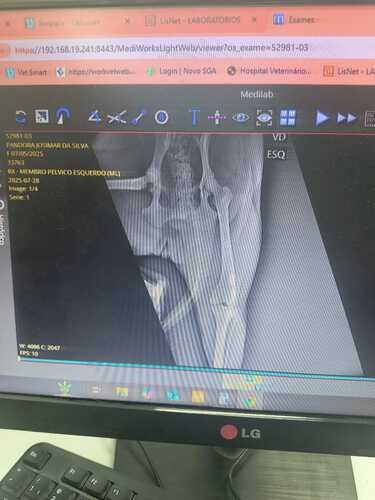

A pandora foi atropelada no Complexo do Alemão, foi socorrida e levada ao hospital de Caxias, onde não há especialista em ortopedia. Foram feitos raio x, ultra e exame de sangue, que apontaram um deslocamento no fêmur além da doença do carr ver tudo

A pandora foi atropelada no Complexo do Alemão, foi socorrida e levada ao hospital de Caxias, onde não há especialista em ortopedia. Foram feitos raio x, ultra e exame de sangue, que apontaram um deslocamento no fêmur além da doença do carrapato. Quando ela foi encaminhada a ortopedia, o Dr. Rômulo colocou seu fêmur no lugar e o imobilizou, porem o caso piorou, o fêmur saiu novamente do lugar e evoluiu para nivel cirurgico. A cirurgia ficou no valor de 2.100$, e o dono da Pandora não consegue arcar com os custos. Além disso, dia 01/08 ela será internada, pois devido a dor do fêmur, ela não tem forças pra evacuar, e está com muitas fezes presas. Ela também sofreu uma hemorragia interna, gerando um coágulo próximo a bexiga. Precisamos de ajuda, com qualquer valor, para que ela possa fazer essa cirurgia o mais rápido possível.